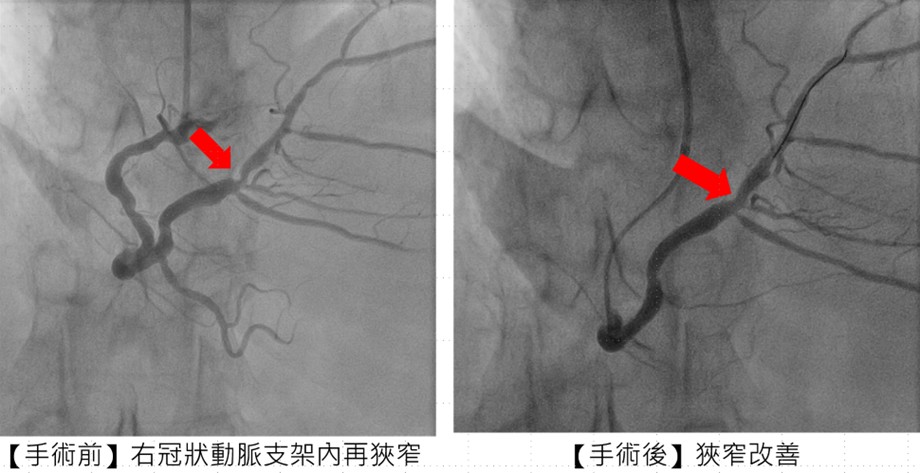

副院長兼心臟科專家陳建鈞醫師進一步說明,張先生病史複雜,支架多次再阻塞,加上長途奔波與壓力,風險極高。團隊經縝密評估,採用「刀片氣球」及「塗藥氣球」治療,不僅打通血管阻塞,也降低再度狹窄的機率,大幅縮短康復時間。手術全程順利,患者隔日即可出院。